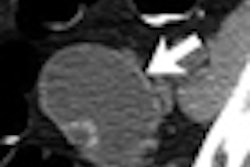

Radiology professionals have found that they can reduce radiation dose in all types of patients by lowering CT x-ray tube settings. But reduced kV doesn't work as well in the obese.

Researchers tried lowering the kV settings for coronary CT angiography studies in overweight and obese patients. While image quality was lower, the technique still produced diagnostic-quality images across the cohort.

But the lower settings didn't work as well in the patients with the highest body mass index numbers, who need more x-ray tube power to penetrate the extra body fat. Learn more by clicking here, or visit our CT Digital Community at ct.auntminnie.com.